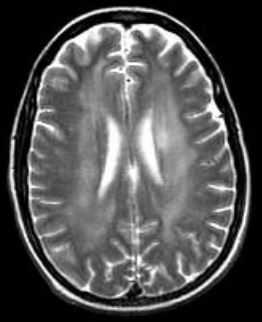

МРТ проявлениями первичного симптомокомплекса является диффузная атрофия с расширением желудочков, что приводит к прогрессирующей деменции и смерти.

МРТ головного мозга. Аксиальная Т2-взвешенная МРТ. Расширение борозд и диффузные очаги.

Прогрессирование атрофии при прослеживании МРТ головного мозга в динамике происходит очень быстро.